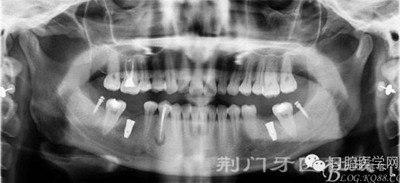

拔除18 28 38 48 后 47 遠中植入支抗釘

因為患者要求半月內(nèi)完成,所以同期植入韓國豋騰4.5*10mm種植體

2月后

3月后